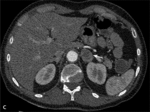

RYCINA. Badanie wykonane 64-rzędowym tomografem komputerowym jednolampowym. Akcja serca podczas badania – 87 uderzeń/min.

Zakres badania – cała klatka piersiowa. [A] Rekonstrukcja VR uwidoczniła prawostronny łuk aorty. [B] Warstwa poprzeczna na poziomie łuku aorty. Widoczne są: niepełny pierścień naczyniowy otaczający tchawicę i przełyk utworzony przez łuk aorty i tętnicę podobojczykową lewą otaczającą tchawicę i przełyk (strzałki). Ściana tętnicy podobojczykowej zawiera blaszki miażdżycowe zwężające jej światło 40%. [C] Warstwa poprzeczna na poziomie nadnercza lewego – widoczny guzek nadnercza lewego (strzałka). [D] Rekonstrukcja VR uwidoczniła prawostronny łuk aorty z częściowym pierścieniem naczyniowym.

- guzek nadnercza lewego o morfologii gruczolaka, bogatolipidowej strukturze o wymiarach 30 × 20 mm (rycina C).